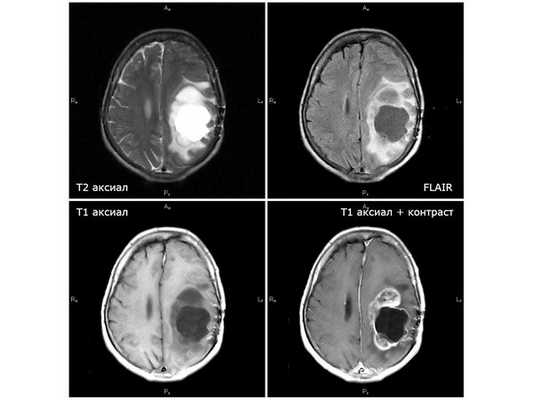

Магнитно-резонансная томография с использованием контрастного препарата является наиболее информативным методом диагностики злокачественных глиом. МР-картина глиобластомы достаточно специфична - это объемное образование с выраженным перифокальным отеком, участком (обычно) периферийного накопления контрастного препарата и центральной некротической зоной. В большинстве случаев диагноз глиобластомы по данным качественных МР-снимков не вызывает каких-либо сложностей, однако ряд патологий имеет схожие МР-характеристики, что требует проведения дифференциального диагноза - метастазы, абсцессы головного мозга и (наиболее сложно) первичная лимфома центральной нервной системы.

В день поступления пациентке выполнена МСКТ (мультиспиральная компьютерная томография) головного мозга без контрастного усиления: выявленные изменения расценены как два объёмных образования в левом полушарии мозга размерами 10*10 мм и 25*35 мм с умеренным отёком вокруг опухоли. МРТ головного мозга с контрастным усилением показало объёмное кистозно-солидное образование размерами 51*53*64 мм с умеренным отёком вокруг опухоли. Проведён онкопоиск: УЗИ органов брюшной полости, малого таза и молочных желез, МСКТ органов брюшной полости с контрастированием и ФГДС (гастроскопия). Первичный очаг не обнаружен.

Первая диагностическая МРТ от 11.08.18: кистозно-солидное объёмное образование с отёком вокруг опухоли